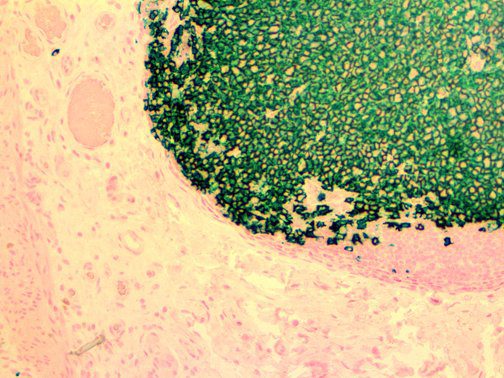

It is the ICU physician who is most likely to witness one of the deadliest manifestations of the abnormal immunological response, the cytokine storm syndrome (CSS). This response is also referred to by some as the cytokine release syndrome (CRS). CSS is characterized by continuous activation and expansion of macrophage and lymphocyte populations, which secrete large amounts of cytokines, causing the cytokine storm. This massive cytokine release is akin to hemophagocytic lymphohistiocytosis (HLH) disease, a syndrome characterized by initial unchecked and persistent activation of cytotoxic T lymphocytes and NK cells.

Clinical and laboratory manifestations of HLH include fever, enlarged liver and/or spleen, neurologic dysfunction, coagulopathy, liver dysfunction, cytopenias (i.e., low levels of erythrocytes, leukocytes, and/or platelets), hypertriglyceridemia, hyperferritinemia, hemophagocytosis, and eventually diminished NK cell activity as the immune system becomes progressively paralyzed. HLH can be familial (primary HLH) or secondary to another disease process (sHLH), such as rheumatic disease, in which it is referred to as macrophage activation syndrome (MAS, characterized by elevated ferritin).